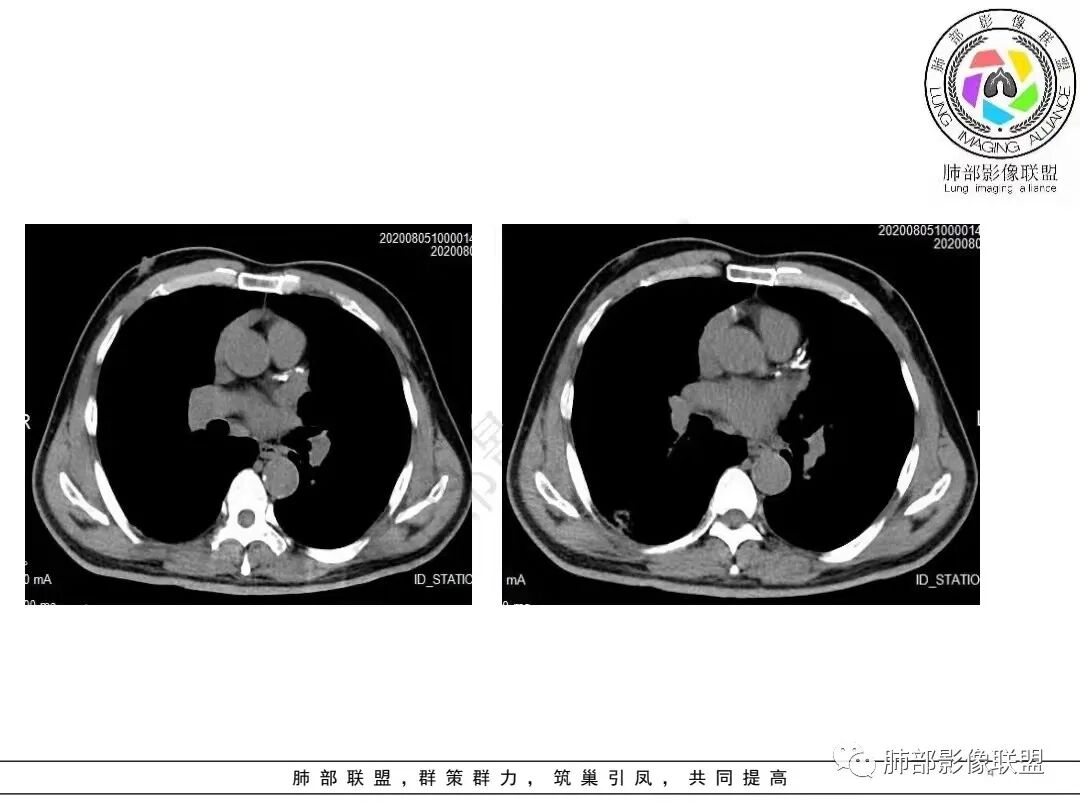

1.病例一:68岁男性,体检发现肺结节,肿瘤标志物CA199、CA50、CEA升高,其中CEA升高显著,超过正常范围的5倍以上。右肺下叶胸膜下结节影,整体较膨隆,部分层面可见锯齿状边缘,边界清晰,周围可见细毛细影,可见血管集束征、胸膜牵拉。密度不均,可见磨玻璃密度区及空泡征,胸膜下脂肪间隙显示不清。增强后显示轻、中度强化。